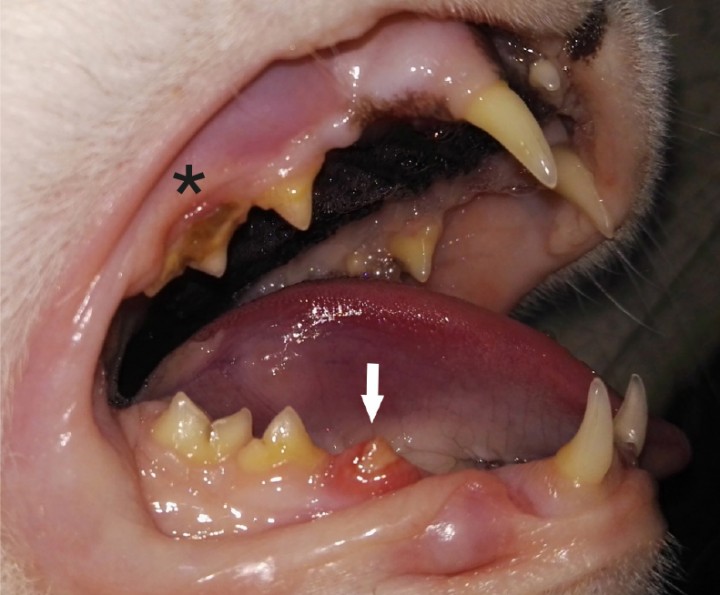

<p> Ausencia aparente de 106 (segundo premolar maxilar dere­cho) y 109 (primer molar maxilar derecho). Cálculo dental de índice 2 en 107 (asterisco). Gingivitis y sobrecrecimiento de la encía que cubre parcialmente el diente 407 compatible con RD (flecha).</p>

Ausencia aparente de 106 (segundo premolar maxilar dere­cho) y 109 (primer molar maxilar derecho). Cálculo dental de índice 2 en 107 (asterisco). Gingivitis y sobrecrecimiento de la encía que cubre parcialmente el diente 407 compatible con RD (flecha).

<p>Ausencia aparente de 206 (segundo premolar maxilar izquier­do) y 209 (primer molar maxilar izquierdo). Cálculo dental de índice 2 en 207 (asterisco). Gingivitis y sobrecrecimiento de la encía que cubre parcialmente el diente 307 compatible con RD (flecha).</p>

Ausencia aparente de 206 (segundo premolar maxilar izquier­do) y 209 (primer molar maxilar izquierdo). Cálculo dental de índice 2 en 207 (asterisco). Gingivitis y sobrecrecimiento de la encía que cubre parcialmente el diente 307 compatible con RD (flecha).